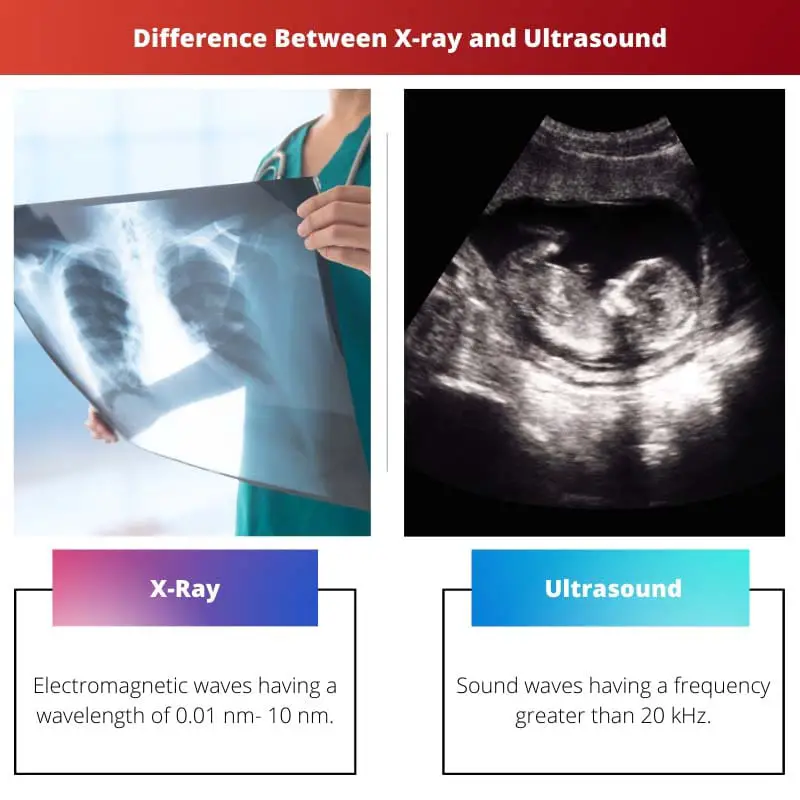

Indulge in the remarkable luxury of our ultrasound vs x-ray-difference between ultrasound and x-ray collection with extensive collections of exquisite images. showcasing the grandeur of music, song, and instrument. perfect for high-end marketing and branding. The ultrasound vs x-ray-difference between ultrasound and x-ray collection maintains consistent quality standards across all images. Suitable for various applications including web design, social media, personal projects, and digital content creation All ultrasound vs x-ray-difference between ultrasound and x-ray images are available in high resolution with professional-grade quality, optimized for both digital and print applications, and include comprehensive metadata for easy organization and usage. Our ultrasound vs x-ray-difference between ultrasound and x-ray gallery offers diverse visual resources to bring your ideas to life. Each image in our ultrasound vs x-ray-difference between ultrasound and x-ray gallery undergoes rigorous quality assessment before inclusion. Advanced search capabilities make finding the perfect ultrasound vs x-ray-difference between ultrasound and x-ray image effortless and efficient. Comprehensive tagging systems facilitate quick discovery of relevant ultrasound vs x-ray-difference between ultrasound and x-ray content. Our ultrasound vs x-ray-difference between ultrasound and x-ray database continuously expands with fresh, relevant content from skilled photographers. Whether for commercial projects or personal use, our ultrasound vs x-ray-difference between ultrasound and x-ray collection delivers consistent excellence.